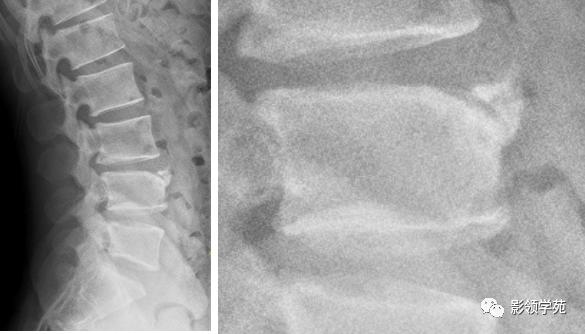

永存性骨骺

又称生理性骨块分离、椎缘骨、锥角离断体边缘骨等。在骨的生长发育过程中,当骺板发育到成熟阶段,其软骨的增殖和成骨活动停止,骺板因某些因素未被骨化,使骨干与干骺端融合障碍而形成。